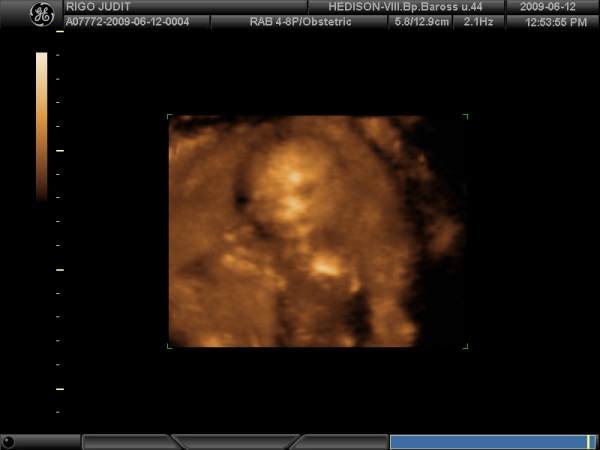

Kismór is jól beletemette az arcát a méhlepénybe, de a kukit azt büszkén mutogatta, úgyhogy Bogyi valószínűleg kislány, mert csak a férfiak tudnak ilyen büszkék lenni a nemiszervükre:I))